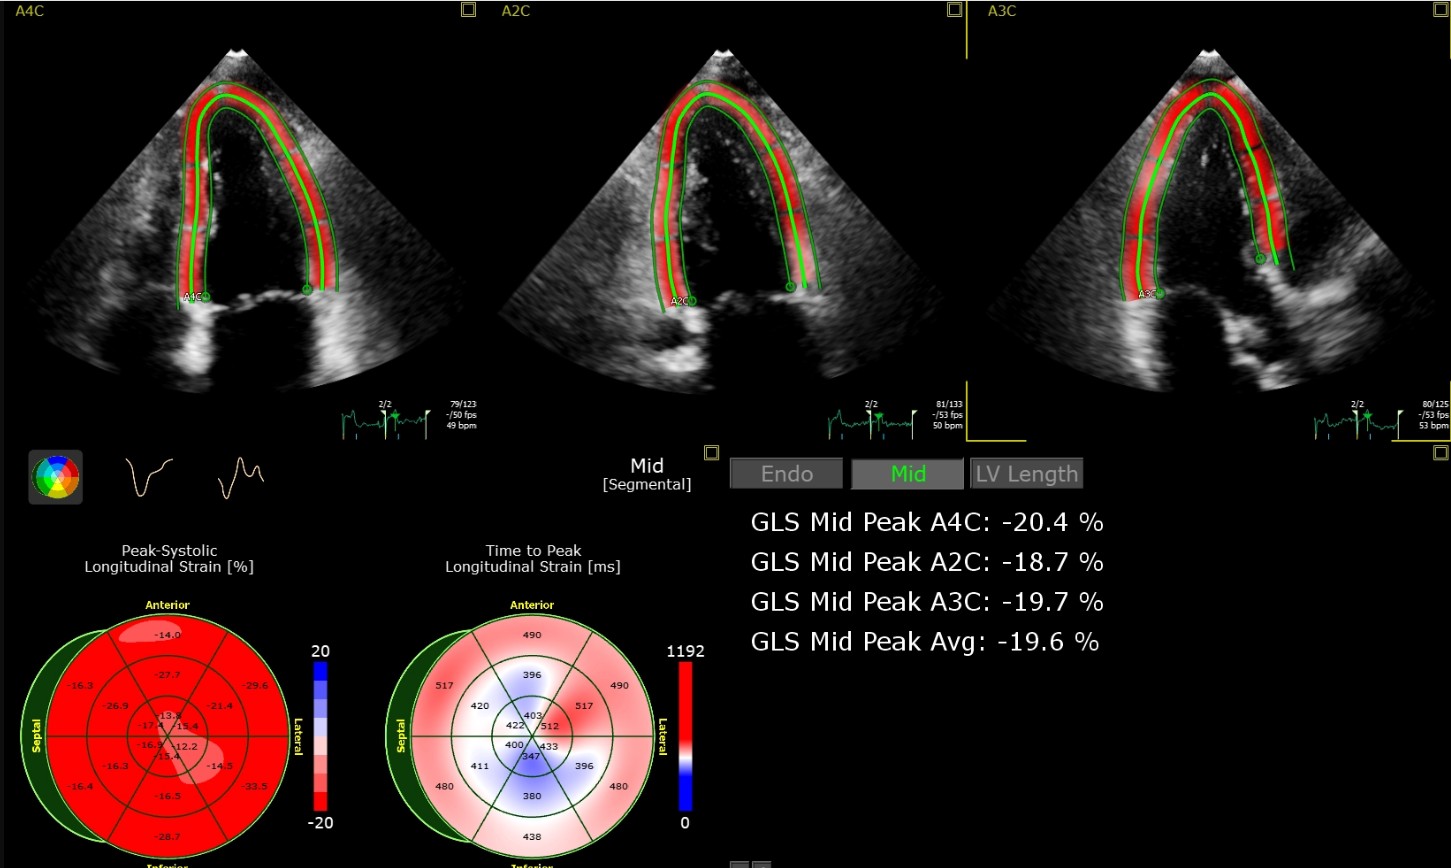

Transthorakale Farbdoppler-Echokardiographie inkl. Gewebedoppler mit modernster Ultraschalltechnik

Dynamische Stress-Echokardiographie zur Belastungsdiagnostik mit Ultraschall unter körperlicher Anstrengung